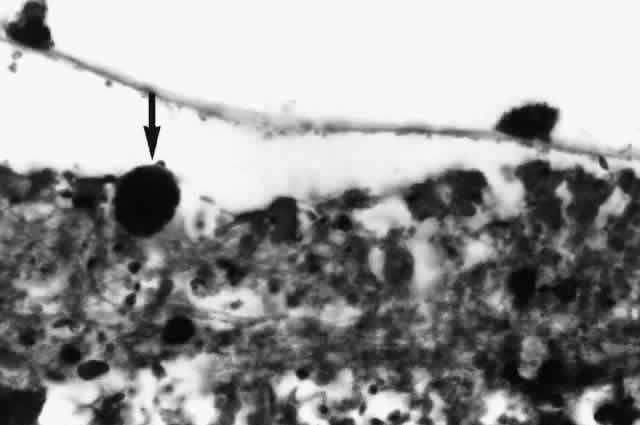

In cases with full-thickness necrosis, the retina appears to have a thick, densely opaque appearance with sharply demarcated borders. There is usually little hemorrhage. There may be inflammatory vascular sheathing, but this sign is not helpful in differentiating ocular toxoplasmosis from other infections, such as CMV retinopathy or syphilis. A prominent inflammatory reaction in the vitreous and anterior chamber has been described by some investigators, while others report little associated vitritis or iridocyclitis.50,51 Histopathologic examination of lesions reveals both trophozoites and cysts in areas of retinal necrosis and within retinal pigment epithelium (RPE) cells (Fig. 5).48 Organisms can be found in fewer numbers in the choroid and vitreous. The optic nerve may also be infected.48,51,52 Although a prominent choroidal inflammatory reaction may be present, there is usually scant inflammatory material in the necrotic retina.48,51

Fig. 5. A prominent Toxoplasma gondii cyst in necrotic retina of a patient with AIDS and ocular toxoplasmosis (arrow). There is little tissue inflammation (hematoxylin-eosin, original magnification [A5];times; 600). (Photograph courtesy of Ben J. Glasgow, MD)